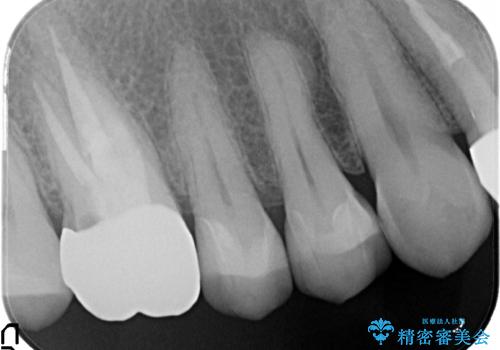

金属だらけの奥歯 根管治療のやり直しとセラミック化

- 神経のある歯を先にセラミック修復し、その後根管治療のやり直しを行う

→最終的にクラウンを製作し、きれいな奥歯を獲得する

インレー(詰め物)は、神経を保存したまま上部を丁寧にやり替えます。

神経の無い歯のクラウン(かぶせ物)は、根管治療を顕微鏡下でしっかりとやり直し、その後に土台の築造とかぶせ物の製作を行うことで今後問題が生じる可能性を可及的に低くできます。